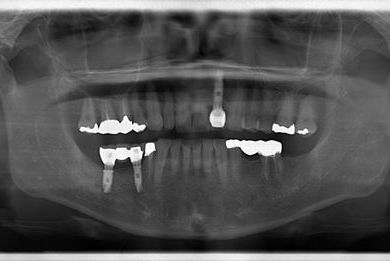

インプラントの症例写真 IMPLANT

骨再生スピードインプラント治療+セラミック治療

| 性別/年齢 | 女性 / 58歳 | ||||||||||||||||||||||||||||||||

| 主訴 | 左上前歯となりがゆらついている。他院でインプラントが必要と言われ、相談に来ました。 | ||||||||||||||||||||||||||||||||

| 治療方針 | 骨再生法によりインプラント治療を可能にする。抜歯と同時にインプラント埋入を行い、治療期間を短縮する。 | ||||||||||||||||||||||||||||||||

| 治療内容 | インプラント3本(抜歯即日スピードインプラント、GBR)、メタルボンドセラミッククラウン1本、ハイブリッドセラミッククラウン4本(ハイブリッドセラミック用土台1本) | ||||||||||||||||||||||||||||||||

| 総治療費 | 1,655,326円 | ||||||||||||||||||||||||||||||||

| 治療期間 | 1年3ヶ月 |